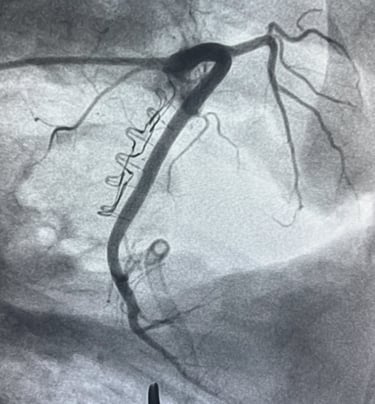

Cinch Annuloplasty Device

Cinch Medical is developing catether-based solutions to functional tricuspid regurgitation.

The Cinch Annulizer will provide quick and easy first line treatment for TR providing a standardized all-comers approach to annuloplasty.

Annuloplasty simplified